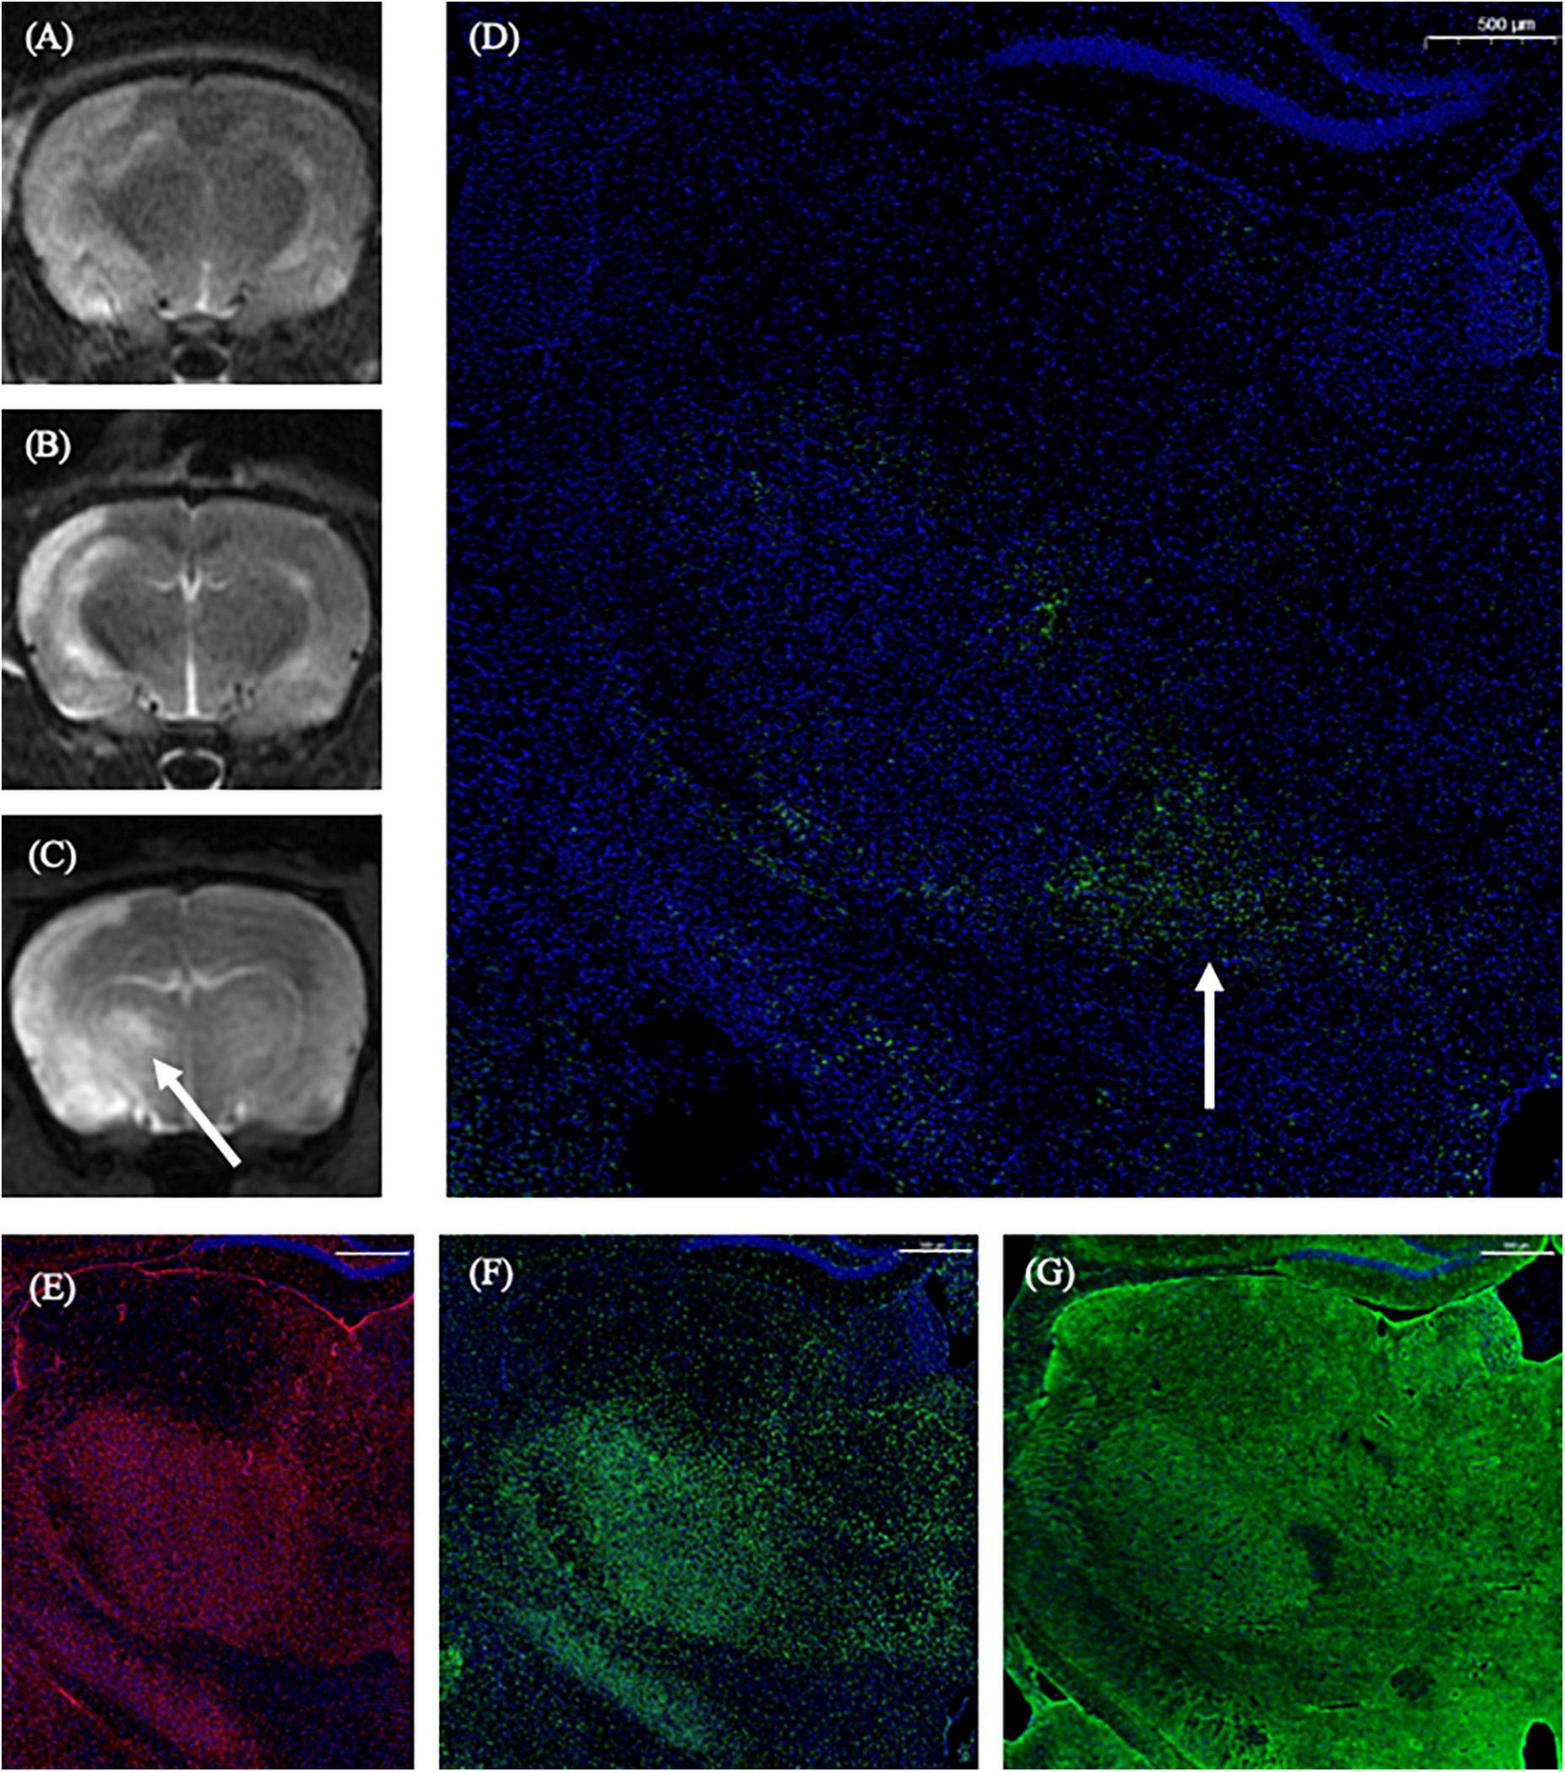

On the 1st day and the 2nd week after MCAO, the ipsilateral thalamus VPN was almost normal at T2-weighted MRI. At the 2nd week after MCAO, the abnormal aggregation area of the contrast medium included almost all the ipsilateral thalamic VPN, which was roughly consistent with the area of astrocytes and microglia proliferation and the AQP4 depolarization. The lateral part of the ipsilateral thalamus VPN was more obvious than the central small cell part. However, for the APP deposition, small cells in the central part of the ipsilateral thalamus VPN were more obvious than in the lateral part. The tendency of the APP deposition in the ipsilateral thalamus VPN was consistent with the one of the contrast medium retention in DCE-MRI, but the location was not the same (Figure 8).

FIGURE 8

The correspondence between DCE-MRI and immunofluorescence staining results in the thalamus VPN. On the 1st day and the 2nd week after MCAO, the ipsilateral thalamus VPN was almost normal at T2-weighted MRI (A,B). At the 2nd week after MCAO, the abnormal aggregation area of contrast medium at 3D T1-weighted MRI (C) included almost all the ipsilateral thalamus VPN, which was roughly consistent with the astrocytes and microglia activation (E,F), and the AQP4 depolarization (G). The tendency of the APP deposition (D, arrow) was consistent with the one of the contrast medium retention in DCE-MRI (C, arrow) in the ipsilateral thalamus VPN. Bar = 500 μm. DCE-MRI, dynamic contrast-enhanced MRI; MCAO, middle cerebral artery occlusion; VPN, ventroposterior nucleus; AQP4, aquaporin 4; APP, Beta-amyloid precursor protein.

The impaired glymphatic system decreases the clearance efficiency of soluble proteins in the brain parenchyma, and the persistence of glymphatic system dysfunction eventually leads to the deposition of harmful proteins in the brain parenchyma. By comprehensive comparison with the results of DCE-MRI and immunofluorescence staining at 2nd week after MCAO, we found that the abnormal aggregation of contrast medium occurred in the whole ipsilateral thalamus VPN region, and the astrocytes and microglia proliferation and the AQP4 depolarization were also in the whole ipsilateral thalamus VPN region. However, the APP deposition was more obvious in the central part of the thalamus VPN, that was, the small cell part. We speculate that the thalamus VPN small cell part is the initial concentration part of the thalamus striatum pathway fiber bundle, which is the more observable site of retrograde secondary degeneration along the axon (Iwai et al., 2015). The APP deposition is more noticeable in the thalamus VPN small cell part, which may be related to the pathological mechanism of retrograde degeneration. While our results also displayed that there was no correlation between histological changes and MRI metrics in all four groups statistically. It may be due to some reasons such as the complexity of MRI signal formation and limitations of MRI signal intensity evaluation. The application of radiomics may get positive results in future study.